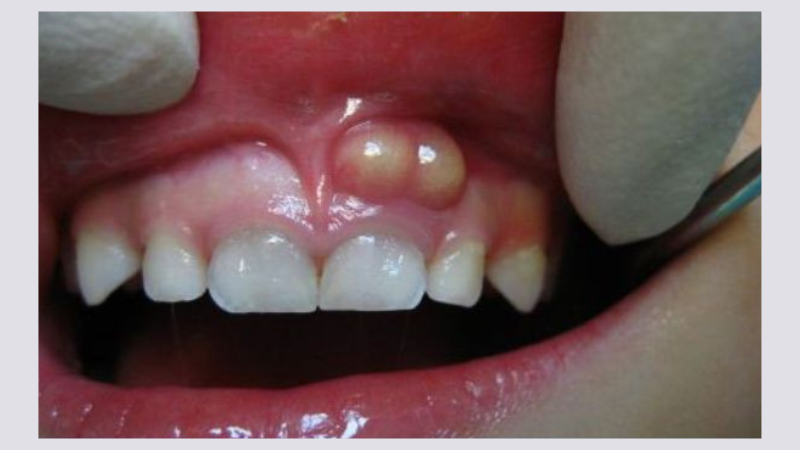

Chân răng nổi cục trắng là hiện tượng phần nướu liền kề với răng xuất hiện u cục nổi hẳn lên trên bề mặt và vùng trung tâm thường có màu sắc sáng hơn các khu vực lân cận. Tùy từng trường hợp mà chúng có thể có kích thước từ vài mm đến vài cm.

U nang răng là trường hợp chân răng nổi cục do xuất hiện bong bóng nhỏ chứa đầy chất dịch mềm. Chúng thường xuất hiện khi chân răng gãy, tạo áp lực lên ổ xương răng hoặc hệ quả của sâu răng lâu năm, nhiễm trùng tái diễn. Đây là một vấn đề lành tính, can thiệp dễ dàng nên chỉ cần xử lý tại phòng khám chuyên khoa là có thể điều trị dứt điểm.

Khi vi khuẩn xâm nhập vào răng hay vùng nướu gần chân răng, chúng có thể gây viêm nhiễm, sưng tấy và hình thành ổ mủ. Từ đó dẫn đến tình trạng nổi cục trắng ở khu vực này. Nếu tổ chức trên bị vỡ ra thì vừa gây hôi miệng, vừa lây lan vi khuẩn sang các khu vực lân cận. Hệ quả là gây viêm xoang, viêm não, viêm xương hàm,...